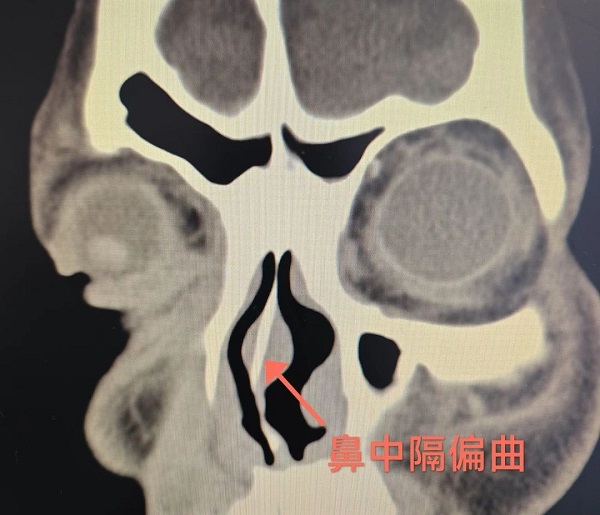

患者鼻子不舒服来院就诊时,常常听到耳鼻咽喉科医生说“你鼻子歪了”。患者非常疑惑,我的鼻好好的怎么歪了。“鼻子歪了”其实是一种鼻腔结构异常,即“鼻中隔偏曲”。

如果把鼻子比作一个“房间”,鼻中隔就是中间的“隔断墙”,将鼻腔分为左右两半。

鼻中隔由软骨和骨头组成,表面覆盖黏膜。

鼻中隔偏曲就是这面“墙”歪了,导致一侧鼻腔变窄,另一侧变宽。